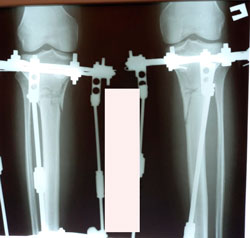

на фиксации

image-22-01-21-05-20-7.jpg

image-22-01-21-05-20-3.jpg

image-19-02-21-11-29-5.jpg

image-19-02-21-11-29-4.jpg